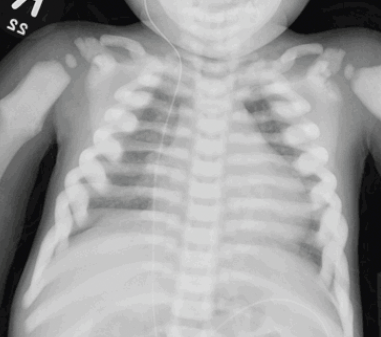

A 2-year-old girl presented with a chief concern of the hematologic abnormalities of anemia and thrombocytopenia.